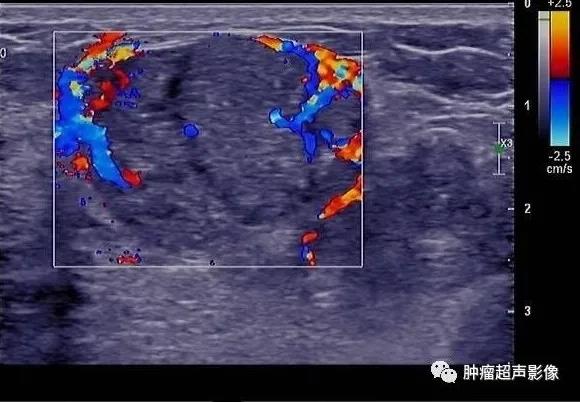

良性叶状肿瘤:女,39,肿块大小4.7㎝,边界清,假包膜,典型裂隙状,血流丰富,表现为典型叶状肿瘤超声表现,但是与交界性难以区分。